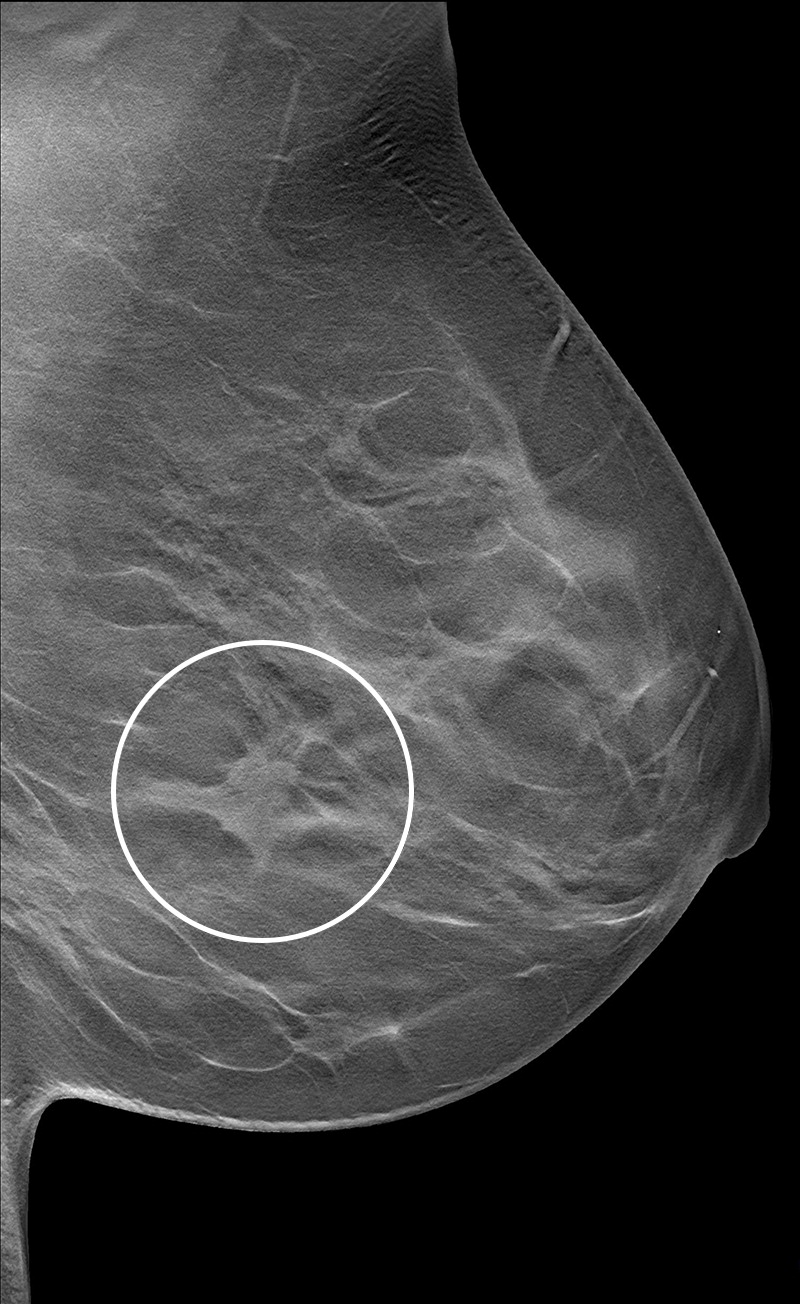

Radiologists have studied and continue to research how breast density plays into breast cancer risk. Previous studies have demonstrated that dense breast tissue masks breast cancers on mammography, and that supplemental imaging such as ultrasound and MRI confirms suspicious findings within dense tissue.

However, advocates for breast density notification say that such messaging impacts many women. Wendie Berg, MD, PhD, from the University of Pittsburgh Medical Center and Magee-Womens Hospital said that for the 40% of women who have dense breasts, cancers are more likely to develop and are more likely not to be seen on the mammogram.

"This allows for individualized, risk-based screening decisions to be made by the patient and her healthcare team," she said." Numerous studies have demonstrated that screening ultrasound in women with dense breasts can detect breast cancers that were missed on the mammogram."